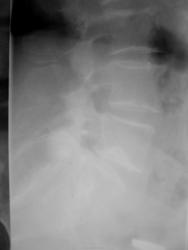

Пациентка около 70 лет, с жалобами на боли в спине направлена на ренгенографию, не совсем понятны изменения L5 на боковом снимке - грыжа Шморля?

Во втором случае направительный диагноз не указан. Грыжа Шморля есть, но она боли не даёт.

Я просто хотела уточнить - это именно грыжа Шморля (т.к. тень высокой интенсивности)?

Вы всё опишите, а для уточнения характера изменений в теле L5 порекомендуйте КТ пояснично-крестцового отдела позвоночника.

Высокой интенсивности потому, что диск пролабирует в позвонок не на всю ширину, уплотнением на такое давление отвечает только часть его. А часть, оставшаяся не продавленной, не оставляет пустого места лучу.)